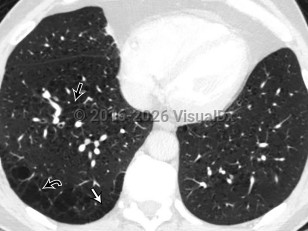

SarcoidosisSarcoidosis